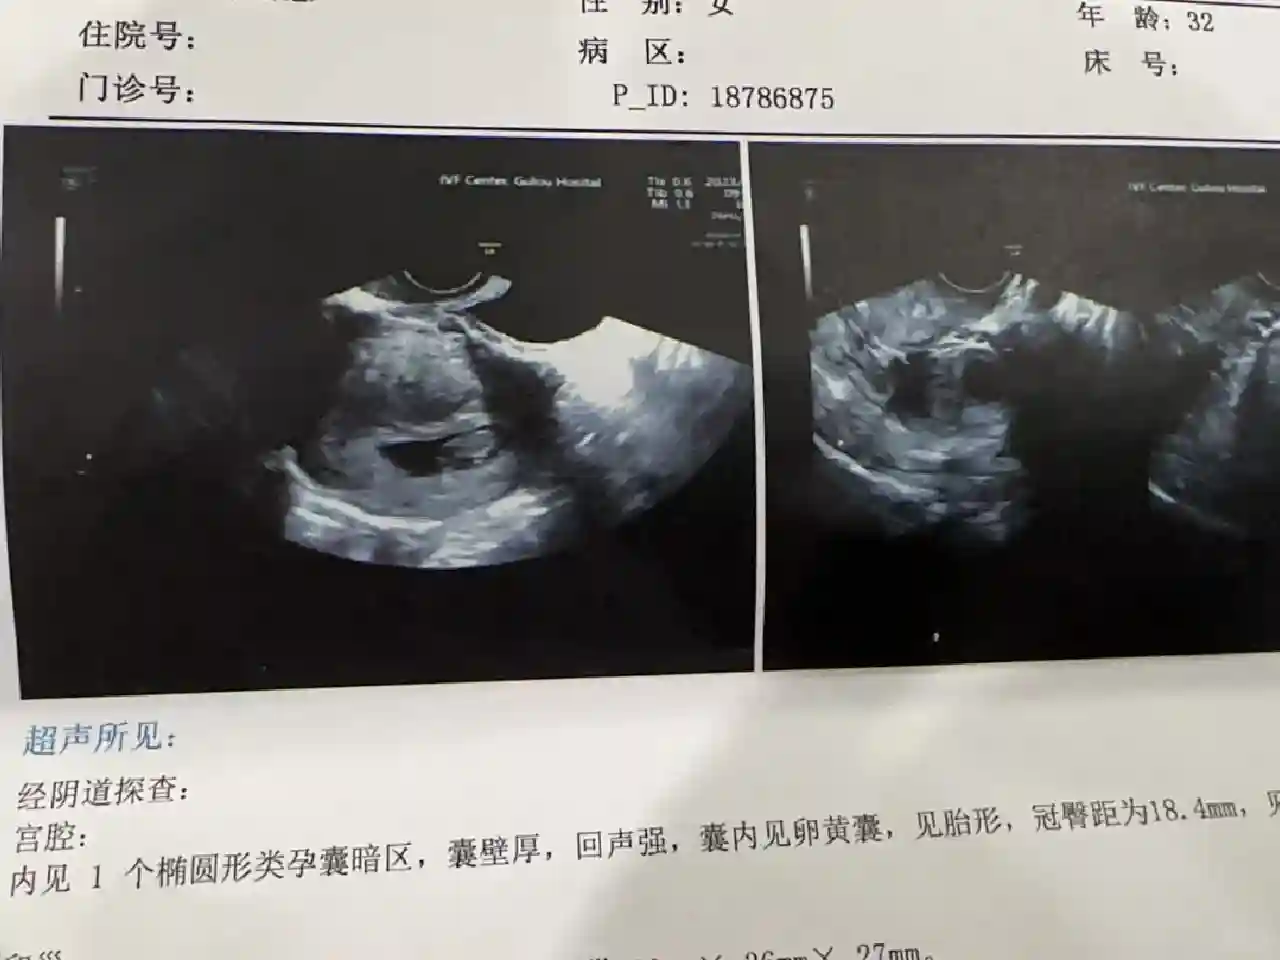

周主任宣告我毕业“以后不用来了”